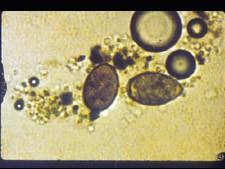

如图所示,三倍体型卫氏并殖吸虫的主要传染源是 ( )A.病犬B.病猫C.患者或带虫且排虫卵者D.甲壳类动物E.螺类

问题 如图所示,三倍体型卫氏并殖吸虫的主要传染源是 ( )

选项 A.病犬 B.病猫 C.患者或带虫且排虫卵者 D.甲壳类动物 E.螺类

答案 C